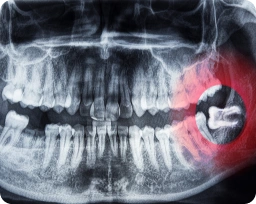

Bevor es zu einem chirurgischen Eingriff an den Zähnen kommt, ist eine umfassende Beratung und Diagnostik unerlässlich. Der Zahnarzt untersucht den Mund gründlich und erstellt einen individuellen Behandlungsplan. Röntgenbilder helfen dabei, die Struktur des Kiefers zu analysieren und mögliche Wunden oder Schäden zu erkennen. Bei Bedarf können Zähne entfernt oder Zahnersatz eingeplant werden, um eine optimale Zahnmedizin zu gewährleisten.